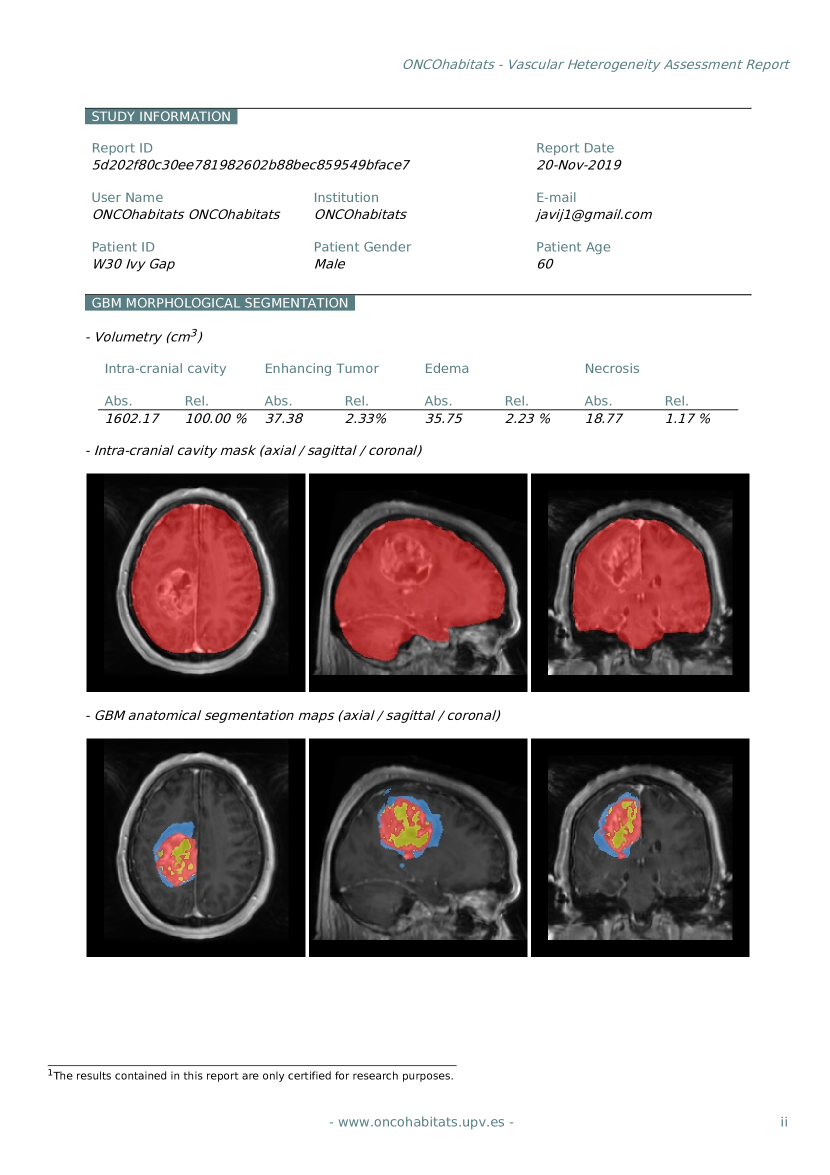

C6 -

An online open-access system for glioblastoma MRI analysis

This contribution consists of the development of a web-based system for the analysis of glioblastomas by means of MRI. The system, named ONCOhabitats (https://www.oncohabitats.upv.es), provides free access to all the methods developed and validated in this thesis, but also to other state-of-the-art algorithms in the field of medical image analysis, to offer a complete solution for the study of glioblastoma from raw unprocessed MRI. ONCOhabitats implements two main services to describe the morphological and vascular heterogeneity of the glioblastoma, generating for each service an automated -based report summarizing all the findings of the study. The details of the system were presented in the journal contribution P8 and conference contribution P9, and the software was registered in the technological catalogue of the UPV, as shown in contributions S1 and S2.

Finally, the methods and technology developed in this thesis have been integrated into an online public open-access platform for its academic use. The ONCOhabitats platform is hosted at https://www.oncohabitats.upv.es, and provides two main services: 1) glioblastoma tissue segmentation, and 2) vascular heterogeneity assessment of glioblastomas by means of the HTS method. Both services, in addition to preprocessed images and segmentation maps, automatically generate a radiological report, summarizing the findings of the study. ONCOhabitats not only offers the scientific and medical community access to leading-edge algorithms for the analysis of these tumors, but gives access to its computational cluster capable to process about 300 cases per day.